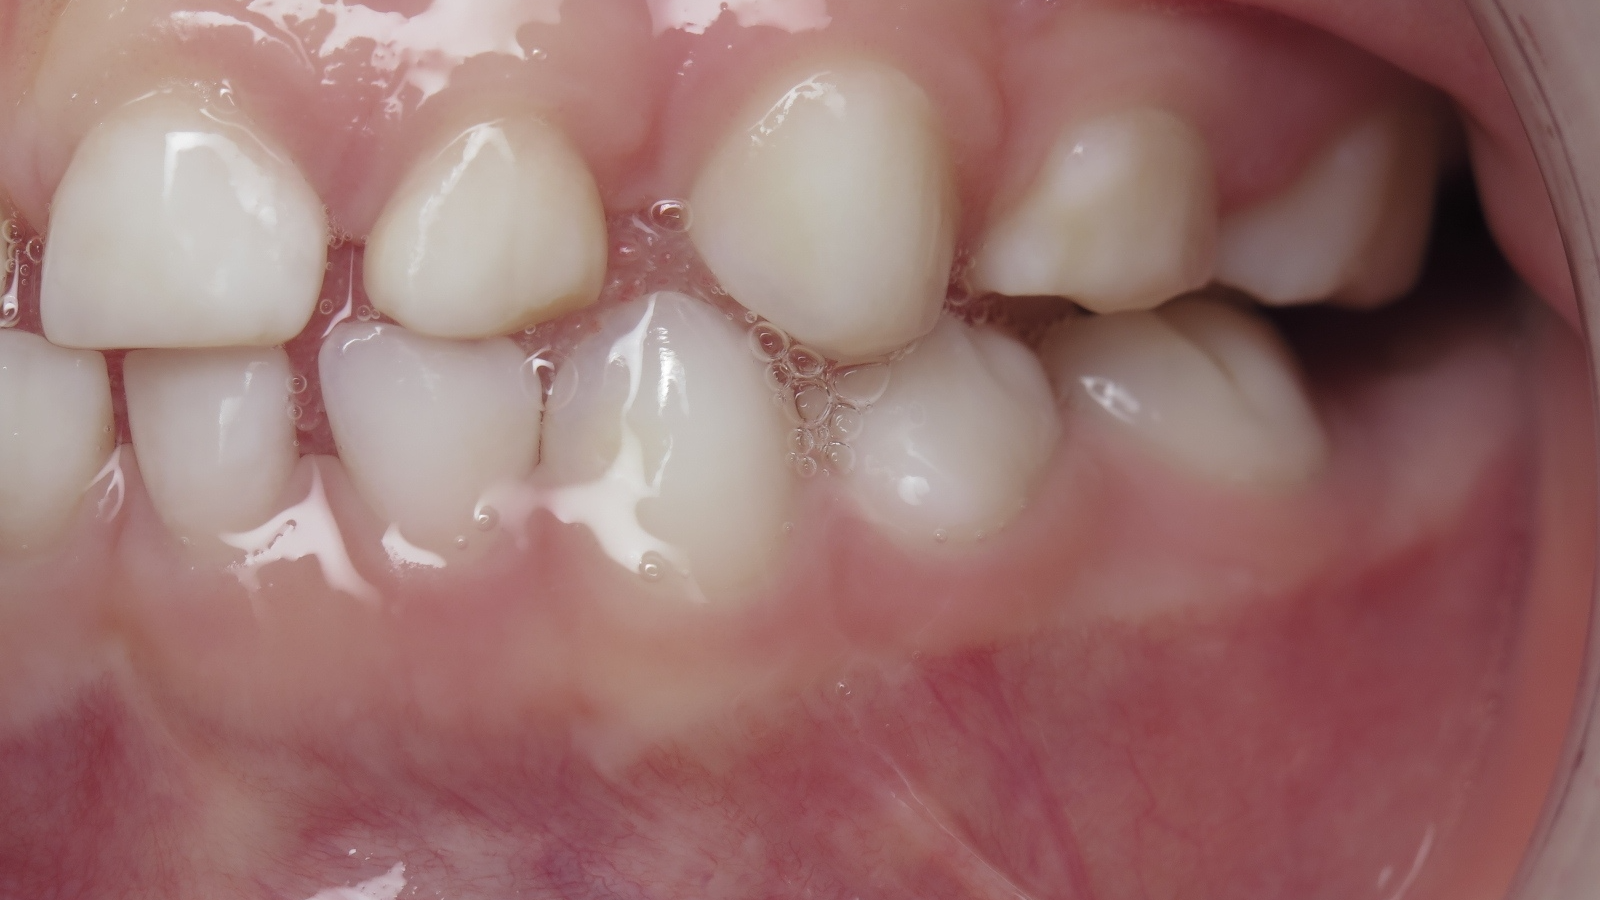

inversion des dents postérieur coté droit

sectionnel multibagues pendant 24 mois

bilan début et en cours de traitement